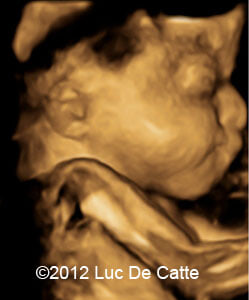

Image 1, 2:  A turricephalic or “tower shaped” skull and frontal bossing

COW_1

COW_1B

• Coronal and sagittal craniosynostosis leading to a turricephalic or “tower shaped” skull

• Prominent forehead (frontal bossing)

The typical craniosyntosis/cloverleaf skull, prominent proptosis and wide great toe suggested Pfeiffer syndrome.